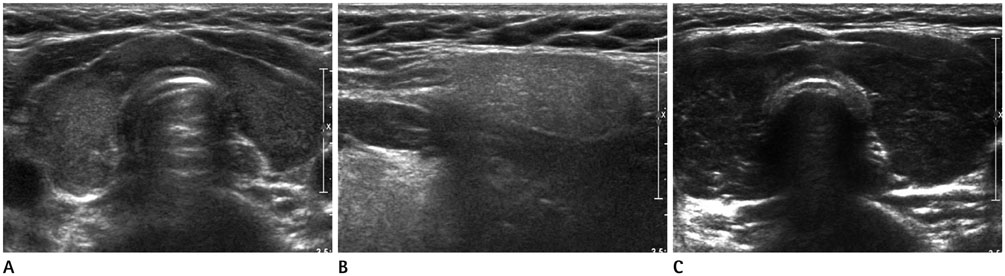

Sonographic Decreased Echogenicity of Thyroid Parenchyma in Asymptomatic Population: Correlation with Thyroid Function and Thyroid Autoimmune Activity

The aim of the study was to evaluate the correlation between decreased echogenicity of thyroid and thyroid hormones or autoantibodies.

From January 2009 to December 2011, 543 patients with decreased parenchymal echogenicity [M:F = 133:410, median age: 42 years (range: 9-82 years)], who did not have solid nodule, symptom or medication related to thyroid and underwent thyroid function test were retrospectively reviewed. Images were classified based on the degree of hypoechogenicity, heterogenicity or thyroid size. 1) Group A: mild decreased echogenicity, group B: marked decreased echogenicity, 2) group Ho: homogeneous echogenicity, group He: heterogeneous echogenicity, 3) group 1: decreased size, group 2: normal size, group 3: increased size. Differences in triiodiothyronyne (T3), free-thyroxine (fT4), thyrotropin (TSH), anti-thyroglobulin antibody (TgAb), thyroid peroxidase antibody (TPOAb), and anti-TSH receptor antibody (TSH-rAb) were evaluated among groups.

T3, fT4, and TSH levels differed between groups A and B (p < 0.001, p = 0.001, p < 0.001). TgAb and TPOAb of group B were higher than group A (p = 0.006, p < 0.001). TPOAb of group He was higher than group Ho (p < 0.001). TSH-rAb and TPOAb of group 3 were higher than group 2 (p = 0.017, p < 0.001).

The patients with findings of markedly decreased, heterogeneous echogenicity or thyroid enlargement may have abnormal thyroid function and autoantibodies. These may facilitate the physicians' decision to order tests for thyroid function and autoimmune activity.